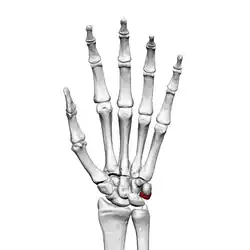

![]() Left hand anterior view (palmar view). Triquetral bone shown in red. | |